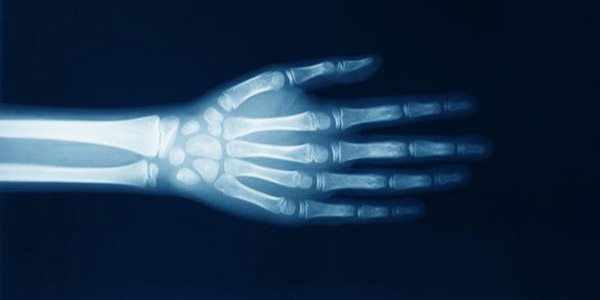

Kanada'daki Alberta Üniversitesi'nden bilim insanları parmak çıtlatan bir kişinin eklemlerinde neler olduğunu ilk kez kayda almayı başardı.

Araştırmayı gerçekleştiren ekibin başında bulunan Greg Kawchuk, ben buna "Parmağımı çek" araştırması adını veriyorum. İstediği zaman parmaklarını çıtlatabilen birinin parmağını çektik ve bu işlem sırasında neler olduğunu MRI video yöntemi ile kayda aldık dedi.

Independent'e konuşan Kawchuk, videoda parmak "çıtlatma" sesinin eklemlerin kaygan kalmasını sağlayan synovial sıvısında aniden oluşan bir hava boşluğundan kaynaklandığını gördüklerini söyledi.

Ortalama 310 milisaniye süren "çıtlama" anını inceleyen uzmanlar, eklem çekildiğinde sıvının doldurmakla yükümlü olduğu alanın genişlediğini ve yeterli sıvı olmadığı için de hava boşluklarının oluşmak zorunda kaldığını söyledi.

Ancak uzmanlar araştırmanın neden bazı insanların parmaklarını istediği zaman çıtlatabildiğini bazılarının ise bunu yapamadığı sorusuna cevap bulamadı. Ayrıca uzmanlar elde ettikleri bu bulguların ışığında parmak çıtlatmanın sağlığa zararlı mı yoksa yararlı mı olduğu konusunda da kesin bir sonuca varamadı.